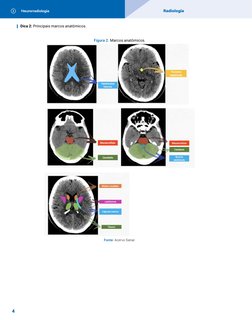

Dica 2: Principais marcos anatômicos.

Figura 2. Marcos anatômicos.

Fonte: Acervo Sanar.